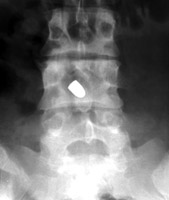

Tumbling Bullet Sign

Post traumatic bone cyst

Two sets of frontal and lateral radiographs, separated only by time, which reveal the "tumbling bullet sign"--which is simply a bullet which changes its location and orientation within a solitary bone cyst. This sign serves two purposes. It is documentation of the evolution of a solitary bone cyst as a corollary of trauma, and reveals the free movement of the foreign body within the confines of the lesion establishing its cystic rather than solid nature. It is similar to the fallen fragment sign.

- Click on the image for a larger versionA - Click on the image for a larger versionB - Click on the image for a larger versionC - Click on the image for a larger versionD